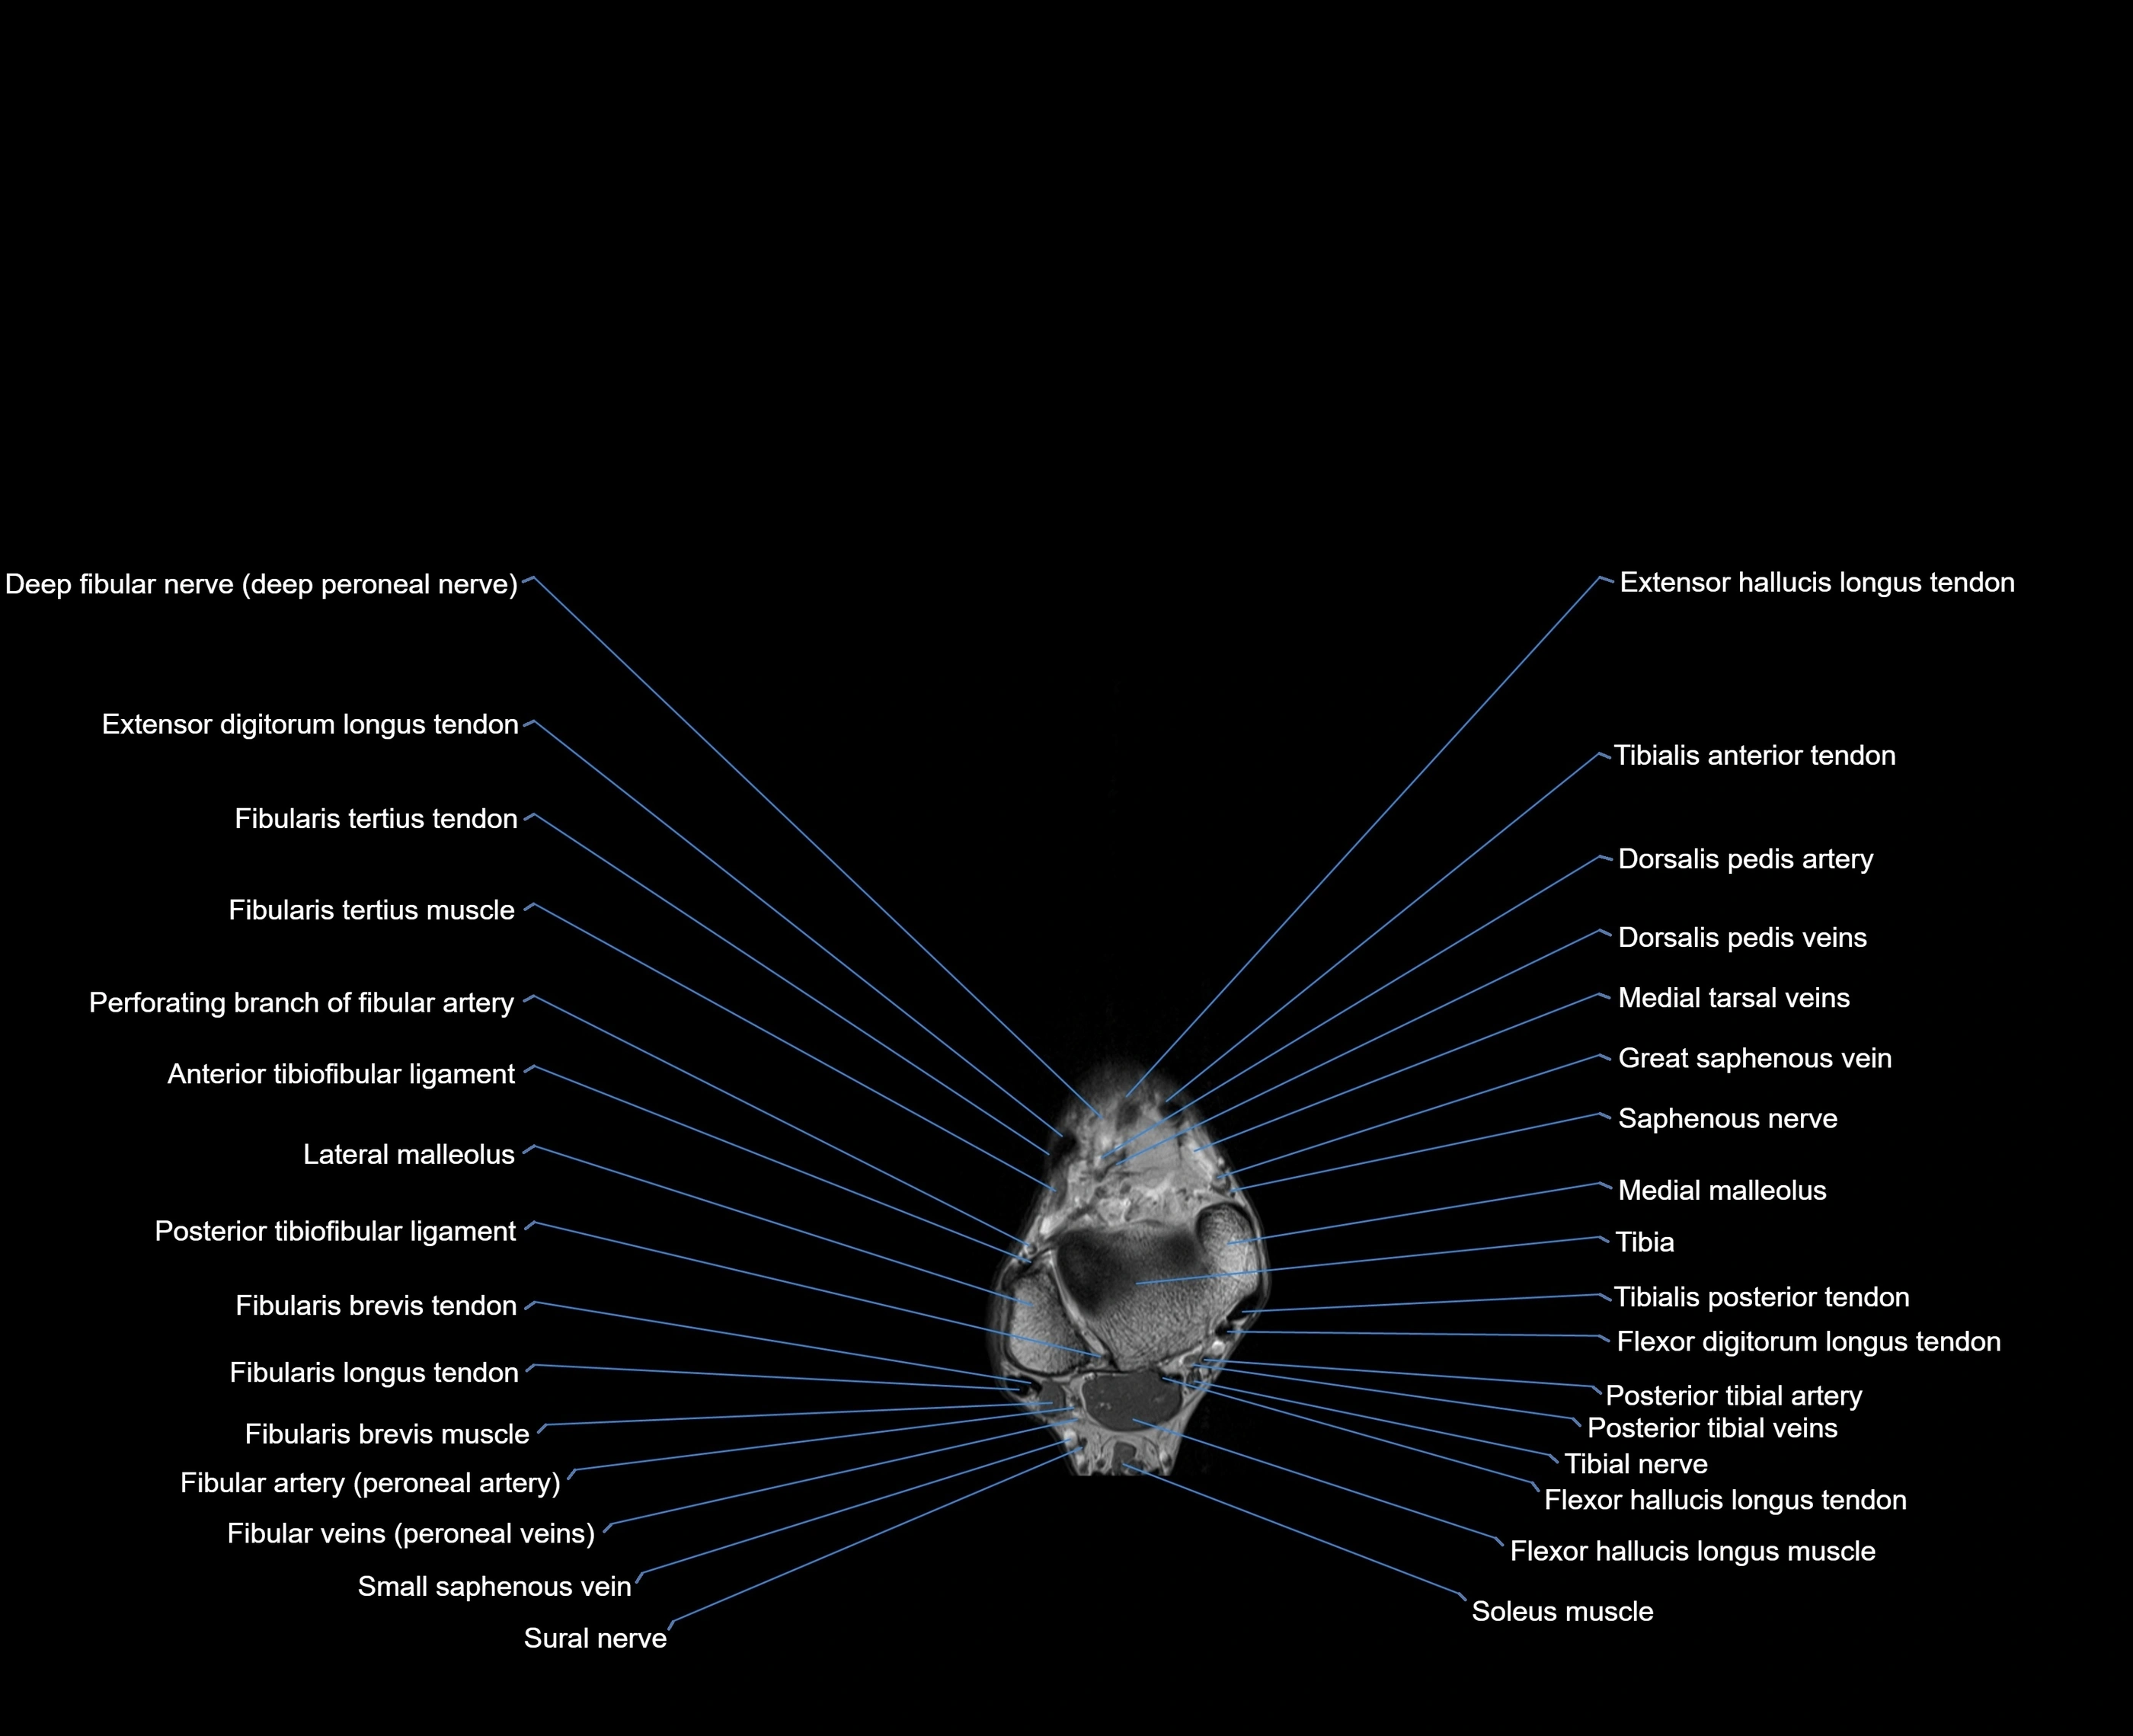

MRI image